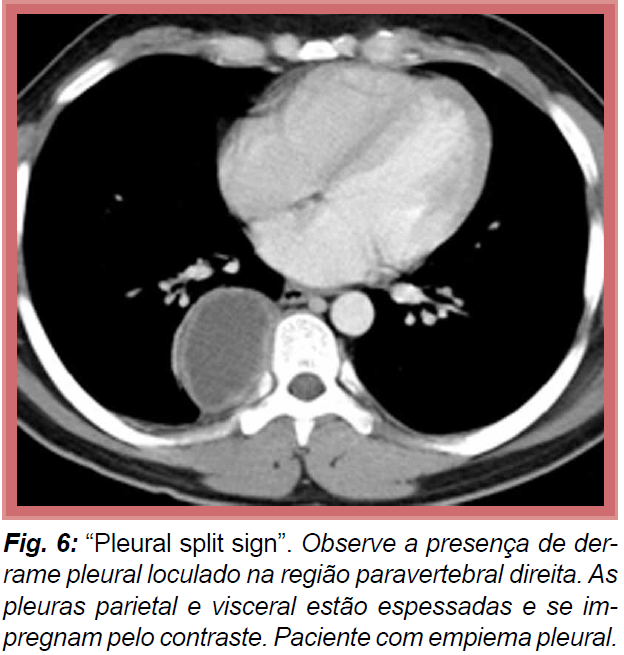

Como dx pleurite na TC de tórax?

Adm contraste EV e realizo a TC. Se houver captação (pleural split sign - ambos os folhetos captam o contraste e estão espessados = pleurite).